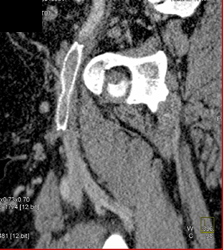

Inferior Vena Cava (IVC) Stent